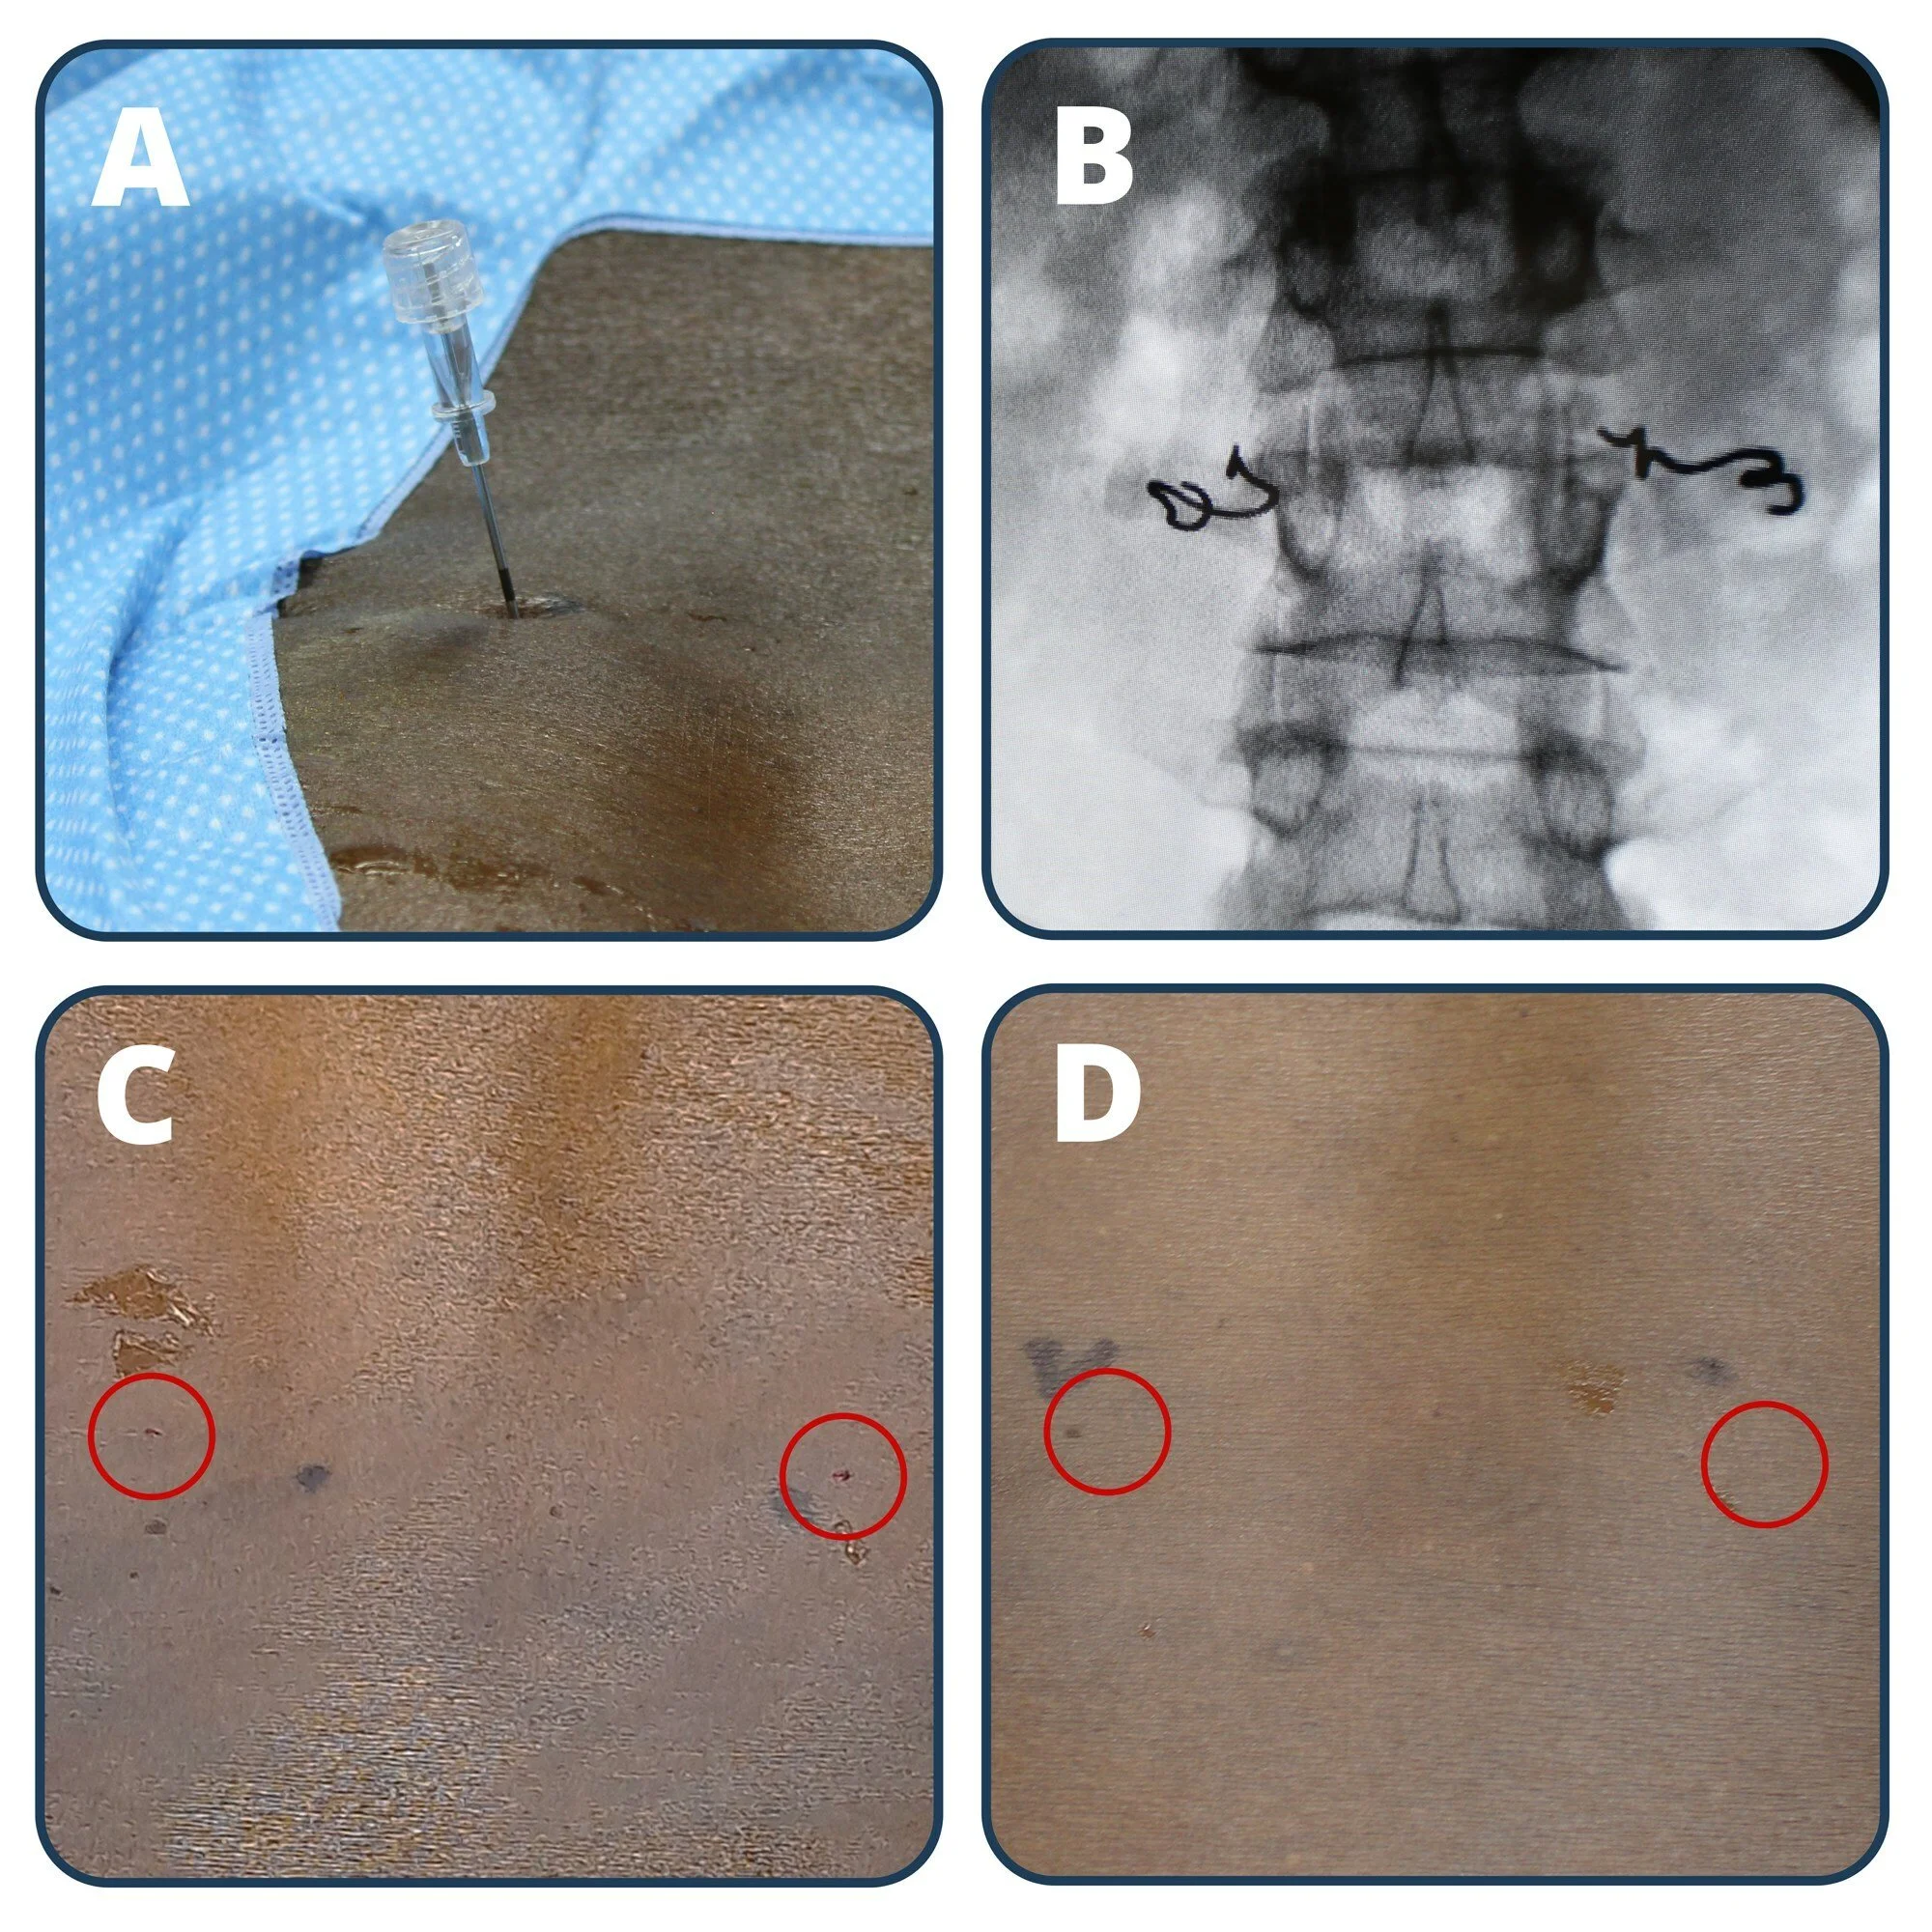

Neuronoff Announces Safety and Functionality Success in First-in-Human Trial of Injectrode for Minimally Invasive Chronic Pain Relief (LIFE study)

The company has successfully completed the first-in-human clinical trial evaluating the safety and effectiveness of its flagship product, the Injectrode, designed to treat chronic pain

This milestone in chronic pain management involved two study participants receiving the minimally invasive injectable electrode, targeting peripheral nerve branches in the lumbar lower back — a key area for novel lower back pain treatments.